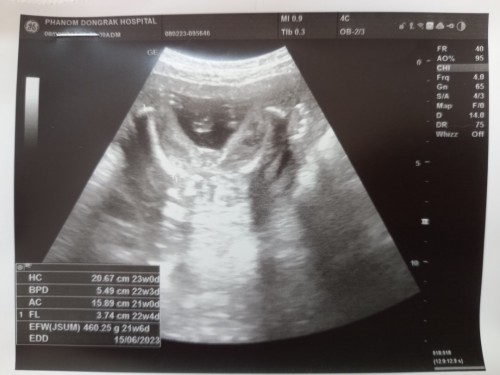

แม่ๆท่านไหนพอจะดูออกมั้ยค่ะว่าเพศไหน เพิ่งซาววันนี้ค่ะ อายุครรภ์ 22+5

คิดว่าผู้หญิงค่ะ ไม่เห็นไข่เลย

ขอบคุณนะคะ หมอเองก็ยังไม่แน่ใจให้รอดูซาวรอบหน้าอีกที

ลุ้นลูกสาวเหมือนกันค่ะ แต่หมอบอกว่าน่าจะชายหมอไม่แน่ใจ ให้รอดูผลซาวอีกที่ครั้งหน้า☺️